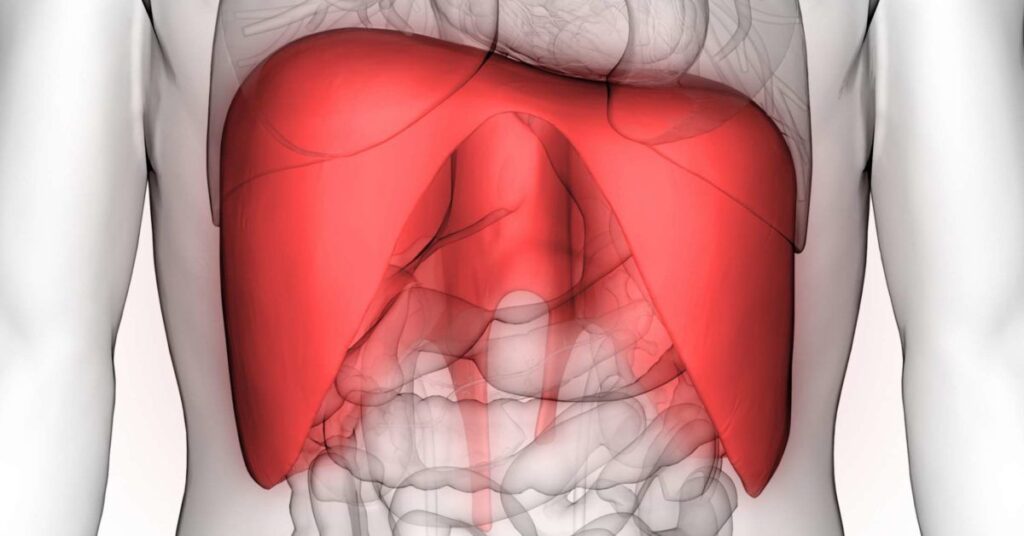

El diafragma, un músculo crucial para la respiración, puede experimentar espasmos, contracciones involuntarias que causan diversos síntomas, desde molestias leves hasta dificultades respiratorias significativas. Estos espasmos diafragmáticos, a menudo asociados con otras condiciones, pueden tener un impacto notable en la calidad de vida del paciente. Comprender sus causas, síntomas y tratamientos es esencial para una gestión adecuada de esta afección.

Las causas de los espasmos diafragmáticos son variadas y abarcan un amplio espectro de factores, desde traumas físicos hasta afecciones neurológicas. Un golpe directo en el pecho o abdomen puede causar una irritación del diafragma, resultando en espasmos. El ejercicio físico intenso, especialmente si no se realiza de manera adecuada o con preparación insuficiente, puede sobrecargar el músculo y provocar contracciones involuntarias. Una causa comúnmente asociada con dolor en el diafragma por ansiedad es la contractura en el diafragma, que se presenta como una tensión muscular persistente.

La hernia de hiato, un trastorno donde parte del estómago sobresale hacia el tórax debido a una debilidad en el diafragma, puede generar dolor de diafragma, así como espasmos y dificultad para respirar. La irritación del nervio frénico, que inerva el diafragma, también puede ser una causa subyacente. Esta irritación puede ser provocada por diversos factores, incluyendo la ingestión de alimentos excesivamente picantes, comer en exceso, o por condiciones más serias como traumas físicos, complicaciones postquirúrgicas, cánceres que afectan la región torácica o abdominal, trastornos neurológicos o infecciones. La conexión entre la ansiedad y el diafragma es notable; el estrés puede contribuir a la tensión muscular, exacerbando el problema y causando dolor diafragma y espalda.